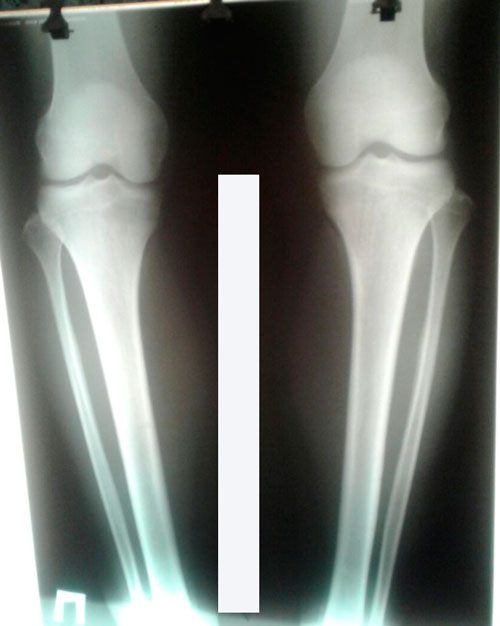

, прикольно))) Я с Алматы, мне 27 лет, приехала 17 января с мужем (отдельное ему спасибо за поддержку), сдала все анализы и назначили операцию на завтра в 12 дня. Операция прошла успешно, мне поставили укол в спину и наркоз в вену, я отдыхала и спала, но все слышала даже могла глаза открыть и посмотреть на врачей. В общем было кайф лежать в операционной потому, что я два дня не могла уснуть, переживала и думала обо всём. В день операции я всё время спала, почти весь день, поставили обез укол в ногу и все до утра отлично спала. Вот на след день было тяжко, хоть и ставят обез укол, но все равно чувствуешь боли в ногах. В этот же день хотела сходить в туалет на коляске, но я опустила ноги и переселе как-то на коляску, но когда сидишь в коляске ноги на полу лежат и очень не удобно. Медсестра когда тебя катает ноги туда сюда бросаются, я в шоке была как так можно на коляске ездить?! Ноги от удара еще больше начали болеть, я расплакалась и закричала. Но медсестры говорили, вот да все девочки жаловались. Надеюсь в будущем купят нормальную и удобную коляску. До туалета дошла с криком, а как сразу хотела пересесть, была жуткая боль в ногах, я потребовала сразу прекратить и обратно унести меня в свою палату. В общем было всё ужасно в этот день, аппетита нет, ноги болят, спина болит, отказалась от ужина. Сегодня 2 день после операции, чувствую себя лучше чем вчера, ночью спала без обез укола, утром взяла себя в руки, получила обез укол и попыталась опустить ноги самостоятельно с помощью пелёнок (кстати надо тянуть пелёнки сильнее и потихоньку опустить ноги, тогда не будет сильно больно). Я опустила ноги и приподняла попочку урааа у меня получилось и это значит, что скоро начну на ходунках ходить